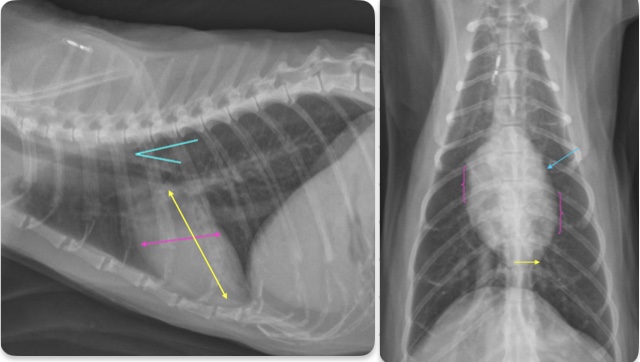

3 features of LAE on lateral

-dorsal displacement of main stem bronchi by a hunchback bump

-increased cd.dorsal cardiac border

-loss of cd.cardiac waist - straightening of cd.cardiac margin

What part of the heart is enlarged

LAE

3 features LVE on lateral

-tall heart (>2/3 DV diameter)

-dorsal displacement of trachea (almost parallel to spine)

-straightening of cd. border of heart

What part of the heart is enlarged?

LVE (technically LAE too) - prof used the same photo for both but outlined different features